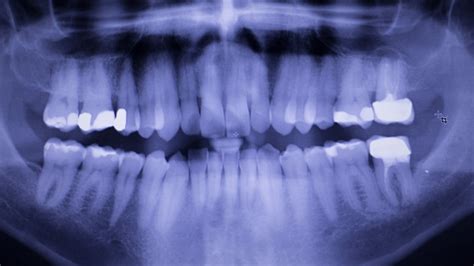

• Diagnosis: Identifying the decay through visual inspection or dental X-rays.

The primary goal of a dental filling is to stop the spread of decay and seal off the affected area to prevent bacteria from re-entering the tooth. When a cavity occurs, the enamel—the hardest substance in the human body—has been compromised. Without treatment, the decay can penetrate deeper into the dentin and, eventually, the tooth’s pulp, leading to infection and severe pain.

When your dentist places a filling, they perform the following steps: